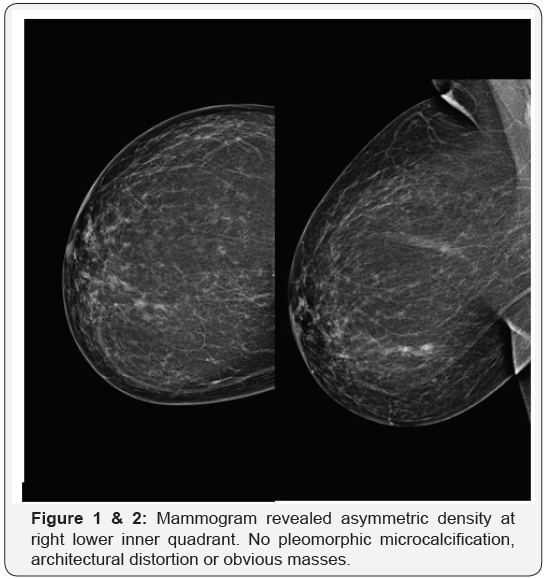

33 year-old female presented herself with pain right breast and history of TB. On clinical examination, the patient had two masses in right breast. The patient was initially examined with mammography which showed asymmetric density at right lower inner quadrant. No pleomorphic microcalcification, architectural distortion or obvious masses (Figure 1 & 2). The routine complementary breast ultrasound was done with a high frequency (8-10MHz) linear array head, which showed two collections noted at 5 and 8-9 o’clock positions (Figure 3 & 4). Finally US-guided fine needle aspiration was done. Also pathological, bacteriological analysis, and polymerase chain reaction (PCR) were done to prove the tuberculous nature of their lesions.